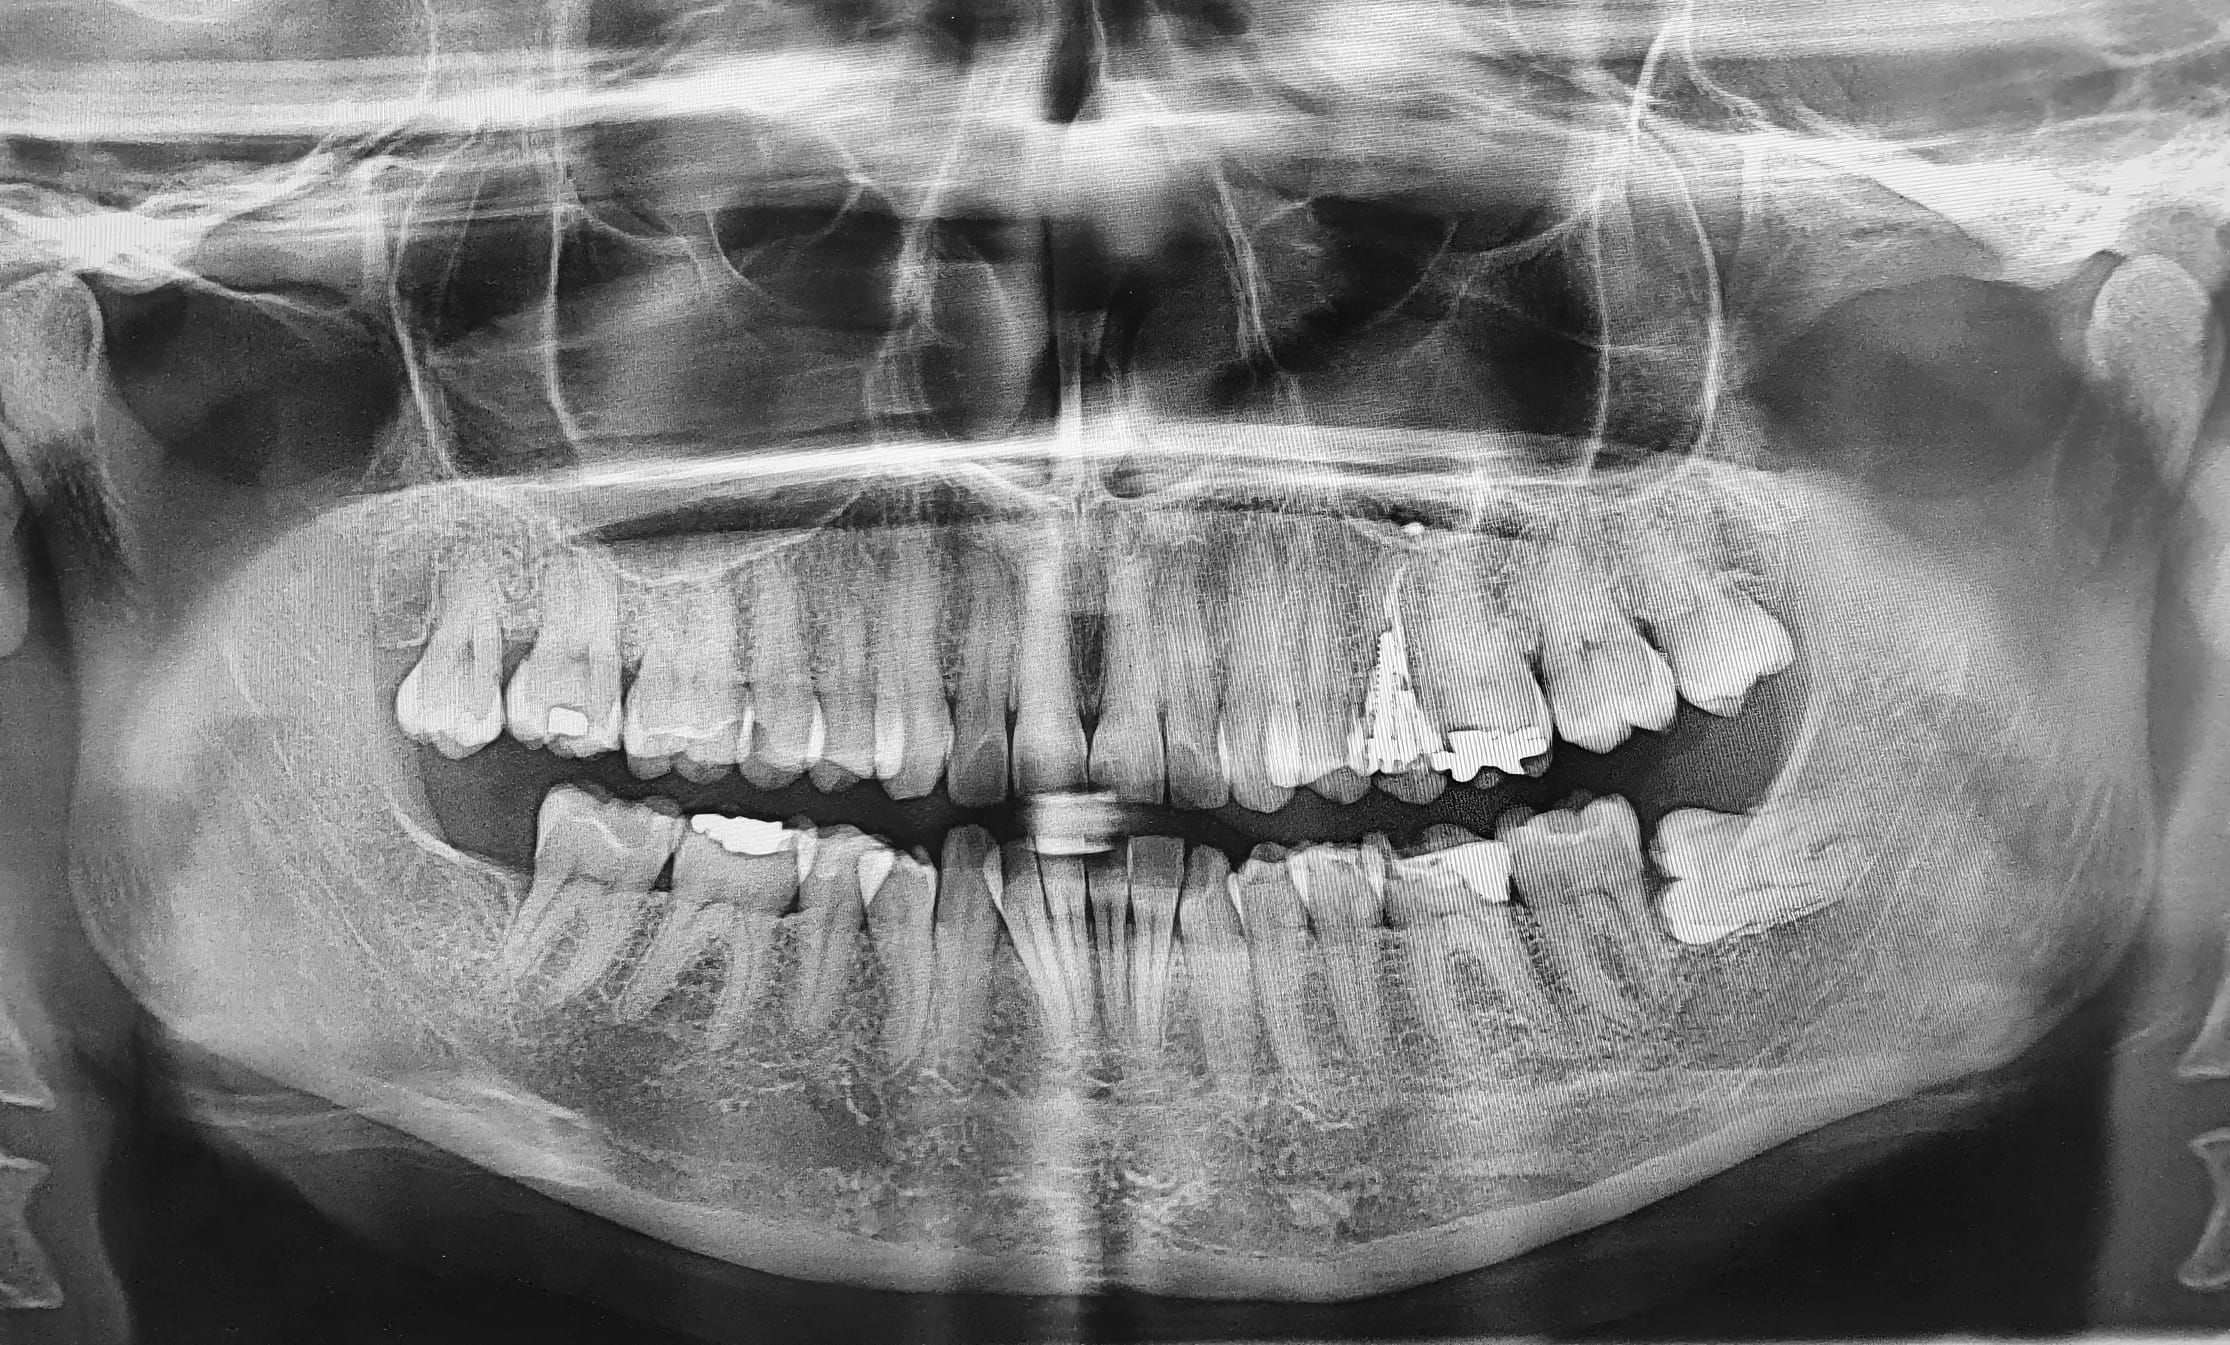

Impacted wisdom teeth

While many believe these teeth require extraction due to overcrowding, the underlying reason can be more serious. This issue can lead to the tooth erupting horizontally, angled inwards or outwards, backwards or forwards. Due to the intricate location of wisdom teeth, it can be extremely difficult to brush this area, thus making bacteria removal a near-impossible task.

As the wisdom tooth struggles to emerge, pressure can be placed on the nearby teeth. Gum tissue and jaw bone can also begin to ache when this occurs. When food and other debris get trapped in and around the loosened gums, the chances of developing an infection become even greater. As the wisdom teeth begin to grow at different angles, they can erupt through the gum without emerging completely. This creates pockets where food can gather and cause infection. Once a wisdom tooth infection arises, it can spread if not treated promptly.